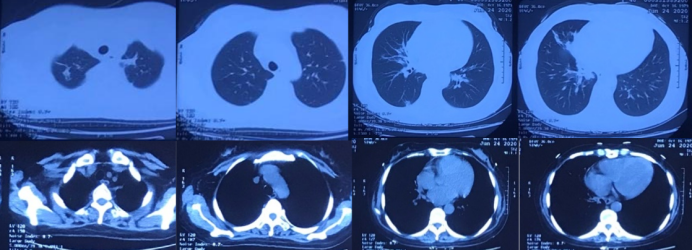

于5月18日复查PCT 0.153 ng/ml;pro-BNP 276.93 pg/ml。复查胸部CT:双肺多发斑片影、结节影及团块影,部分伴空洞,与前片对比部分病灶有所减小(图5。患者咳嗽、咳痰症状较前明显缓解,体温正常,鼻导管吸氧1 L/min,经皮血氧饱和度95%以上。右小腿皮肤破溃范围明显减小(图6),大部分愈合。患者于5月19日出院,院外嘱其口服利奈唑胺片、环丙沙星片。出院1月后随访,患者无明显咳嗽、咳痰症状,复查胸部CT示两肺病灶明显吸收(图7)

5  复查胸部CT2020-05-18

7  出院后复查胸部CT